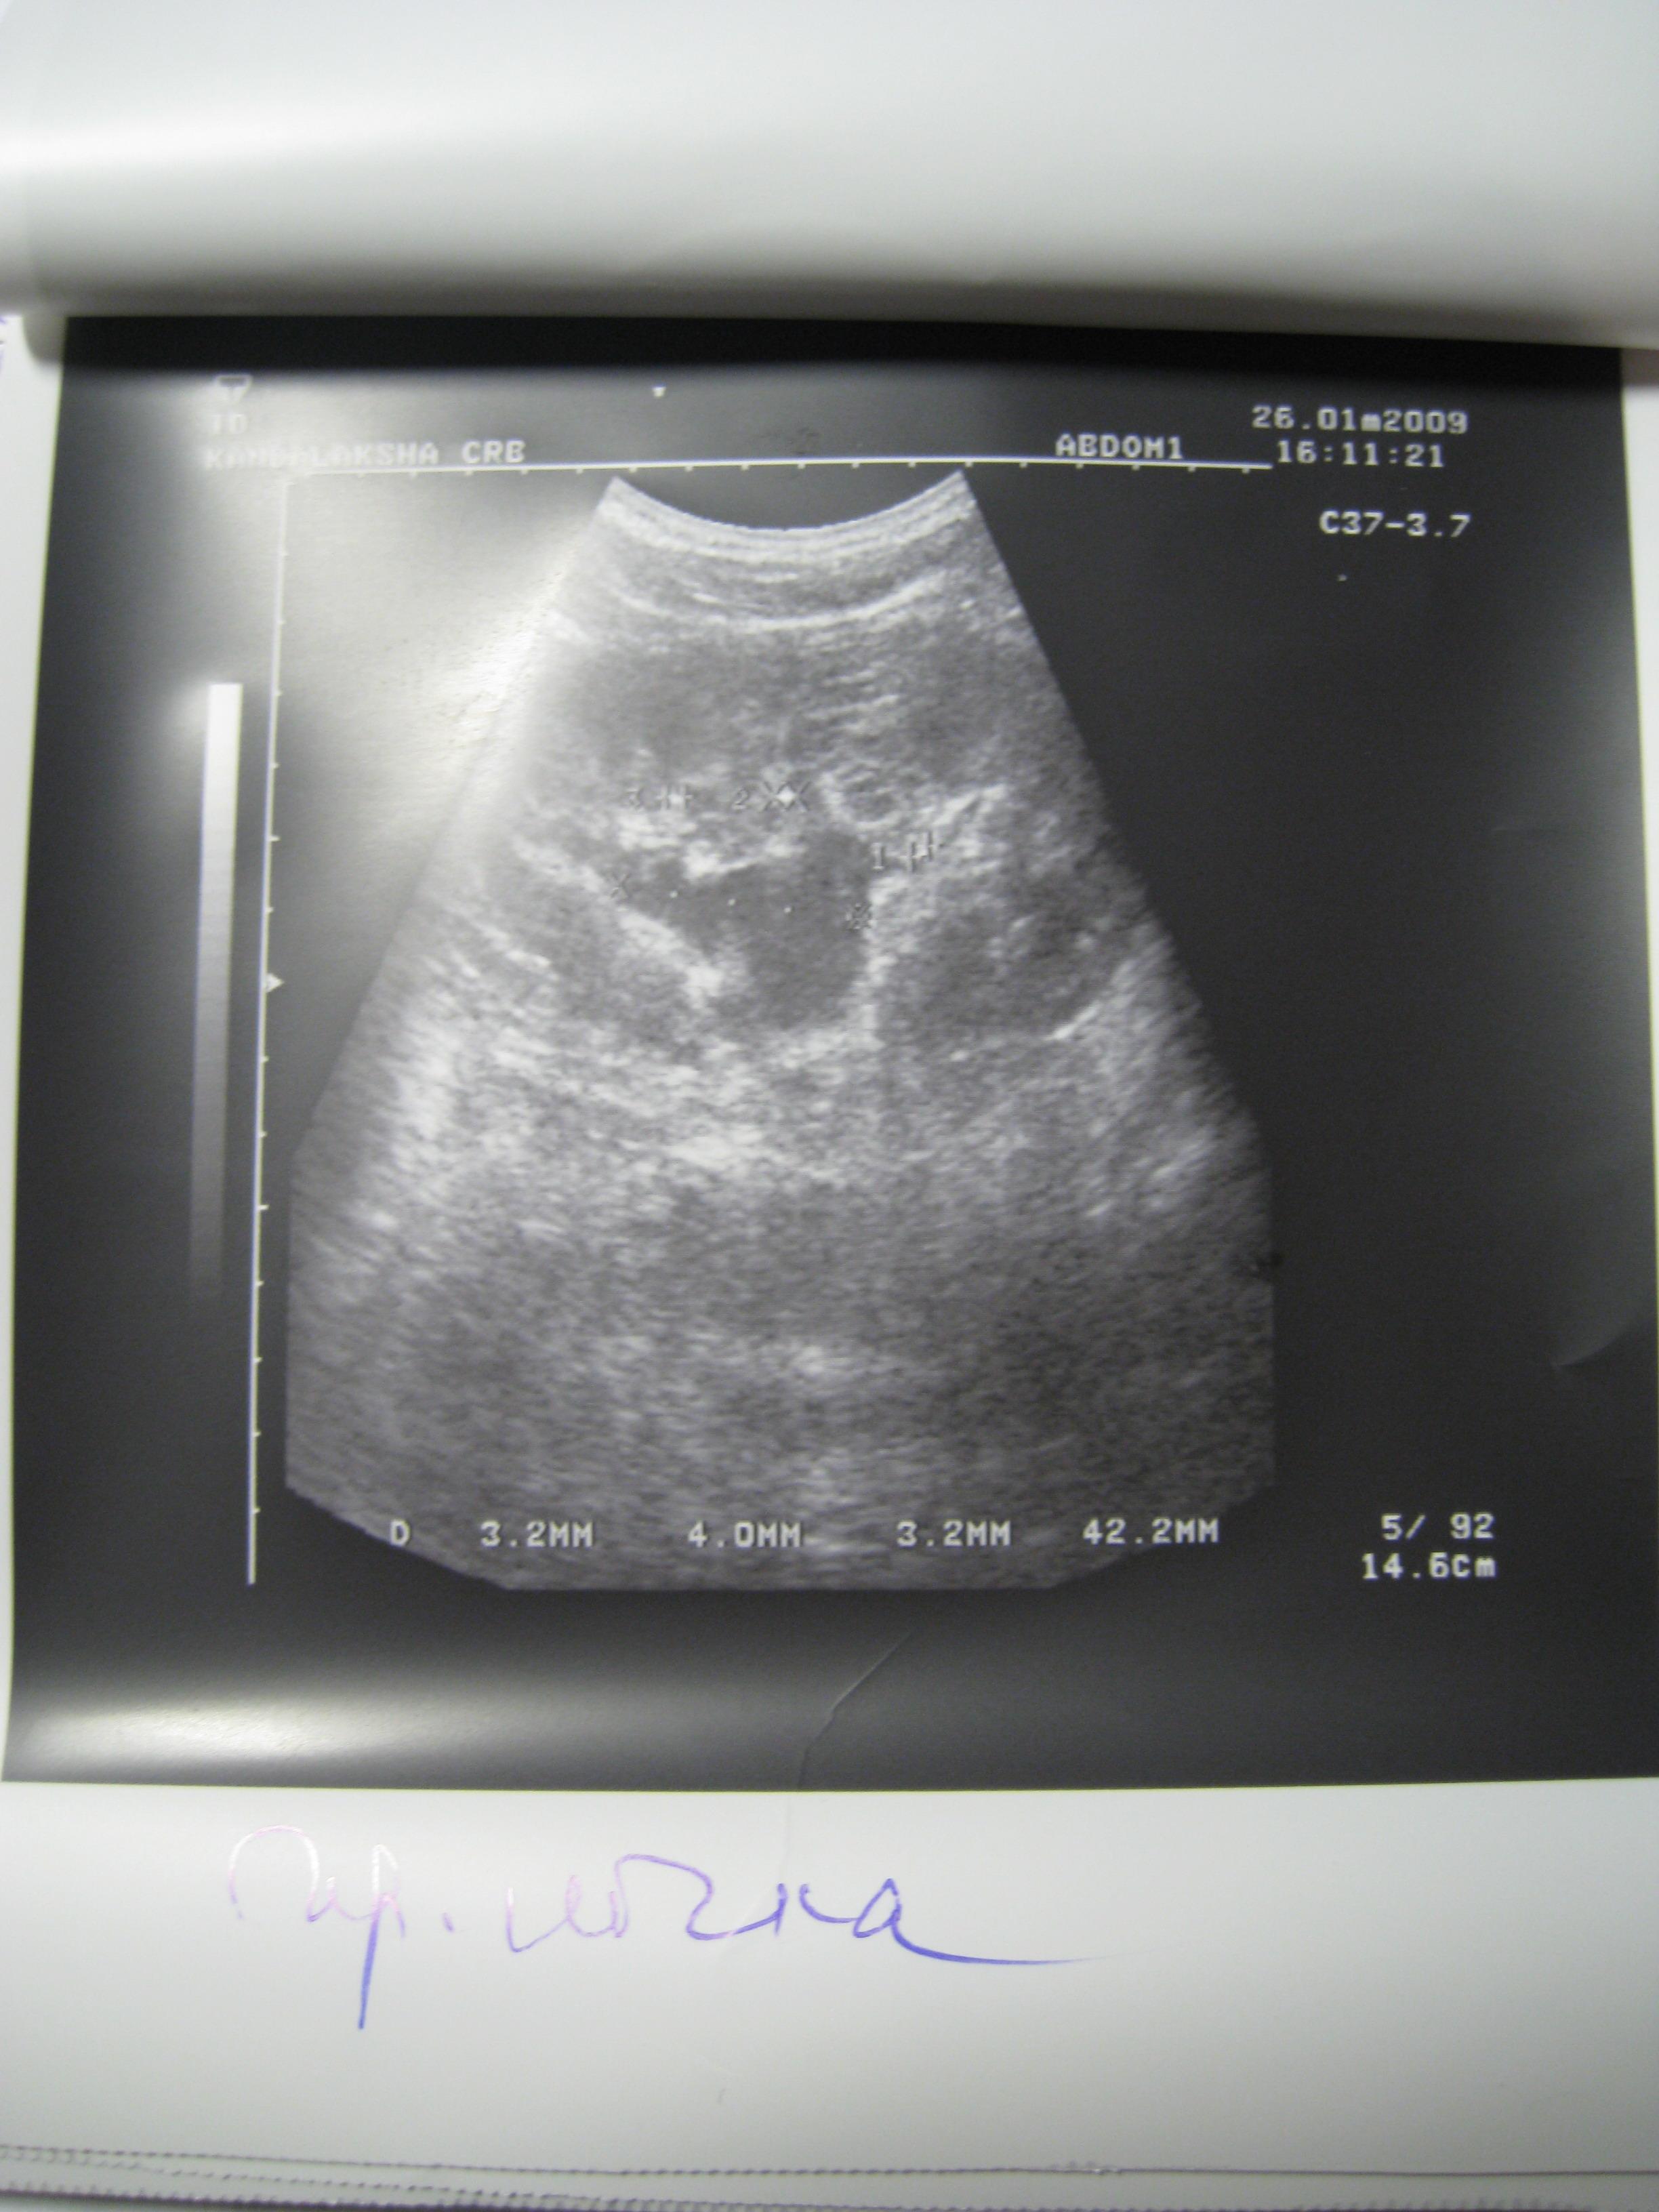

Доктор здраствуйте! мне 23 годаОколо полугода назад лежал на обследовнии в нефрологии,где был посиавлен диагноз:хр,пиелонефрит обеих почек,МКБ,микролиты обеих почек 2-4мм,наиболее крупный справа 4 мм!Было рекомендовано:курсам пить пролит,цистон,урологические сборы и тд!Все ето я принимал,почки особо не беспокоили если тока изредка небольши тупые боли в пояснице по утрам и все!Вчера решил сделать узи почек:диагноз был поставлен следующий:гидронефроз правой почки 1 степени,(врач сказал что лоханка в правой почке увеличена до 40 мм из за МКБ,лоханка левой почки 18 мм,остальные параметры в норме)микролиты обеих почек 2-4 мм,хр,пиелонефрит обеих почек особых жалоб у меня нету на данный момент!количество мочи в течении дня нормальное,удалось сдать анализы мочи(общий и по Нечипаренко.В общем анализе обнаружили немного белка,если нужны цифры могу написать завтра,но сказали что не очень много)по Нечипаренко все в норме!Более полное обследование чем узи нет возможности сделать!уролог прописал пить цистон ,уролесан и сборы трав пить и все!посоветуйте что нужно и можно делать в моей ситуации!снимок узи: